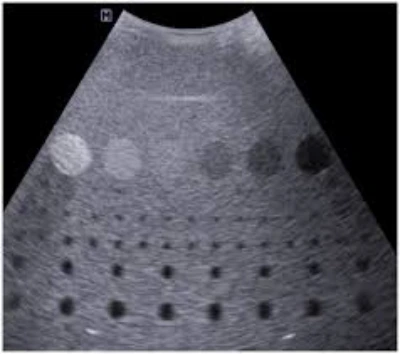

O transdutor é um componente essencial nos equipamentos de ultrassom, responsável por converter os impulsos elétricos em ondas sonoras de alta frequência .

Ele emite e recebe os sinais ultrassônicos, permitindo a formação das imagens utilizadas nos exames médicos.

Quando o transdutor apresenta falhas, a qualidade das imagens é comprometida, impactando diretamente no diagnóstico e tratamento dos pacientes.

A falha nos transdutores pode resultar em imagens distorcidas, perda de resolução, ruídos indesejados e até mesmo a impossibilidade de realizar exames .